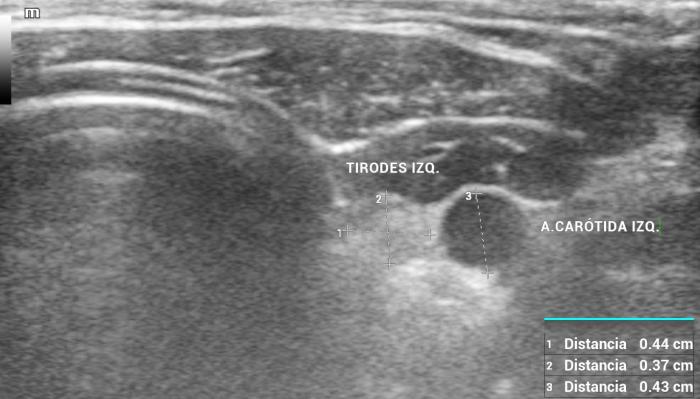

La localización anatómica superficial de la glándula, junto con su estructura relativamente uniforme, facilita su identificación mediante ultrasonografía de alta resolución. Entre los reparos anatómicos más importantes para su localización se encuentran las arterias carótidas comunes (laterales), la tráquea (medial) y los músculos esternotiroideos (ventrales), mientras que el esófago puede constituir una referencia dorsal del lóbulo izquierdo15 (Figuras 3 y 4).

El uso de estructuras vasculares adyacentes como referencias anatómicas ha sido una estrategia útil en ecografía veterinaria para estandarizar las mediciones de órganos pequeños como la glándula tiroides. En este contexto, Bandula Kumara et al. (2019) propusieron la medición de la relación entre el diámetro tiroideo (TD) y el diámetro de la arteria carótida común (CCA) como una forma práctica de evaluar el tamaño de la glándula en perros clínicamente normales (Figura 5A-B).

Los autores realizaron un estudio en el que midieron el diámetro anteroposterior de los lóbulos tiroideos y el diámetro externo de la CCA en cortes transversales obtenidos a nivel del cuello medio. Encontraron que esta relación se mantiene relativamente constante entre razas y tamaños corporales, sugiriendo que puede ser utilizada como parámetro de referencia ecográfica. Específicamente, en perros adultos sanos, la relación TD/CCA fue de 1.74 ± 0.40 (rango 1.11–2.43)6. Si los valores se encuentran por debajo del rango normal pueden ser considerados potencialmente indicativos de hipoplasia tiroidea o atrofia glandular.

Una ventaja de esta relación es que la arteria carótida común es fácilmente identificable ecográficamente, presenta un diámetro estable y poco variable en condiciones fisiológicas, y se ubica en estrecha proximidad con la glándula tiroides. Esto la convierte en una excelente estructura de referencia para normalizar mediciones entre individuos de diferente tamaño corporal, permitiendo evaluaciones objetivas en poblaciones mixtas de perros de compañía.